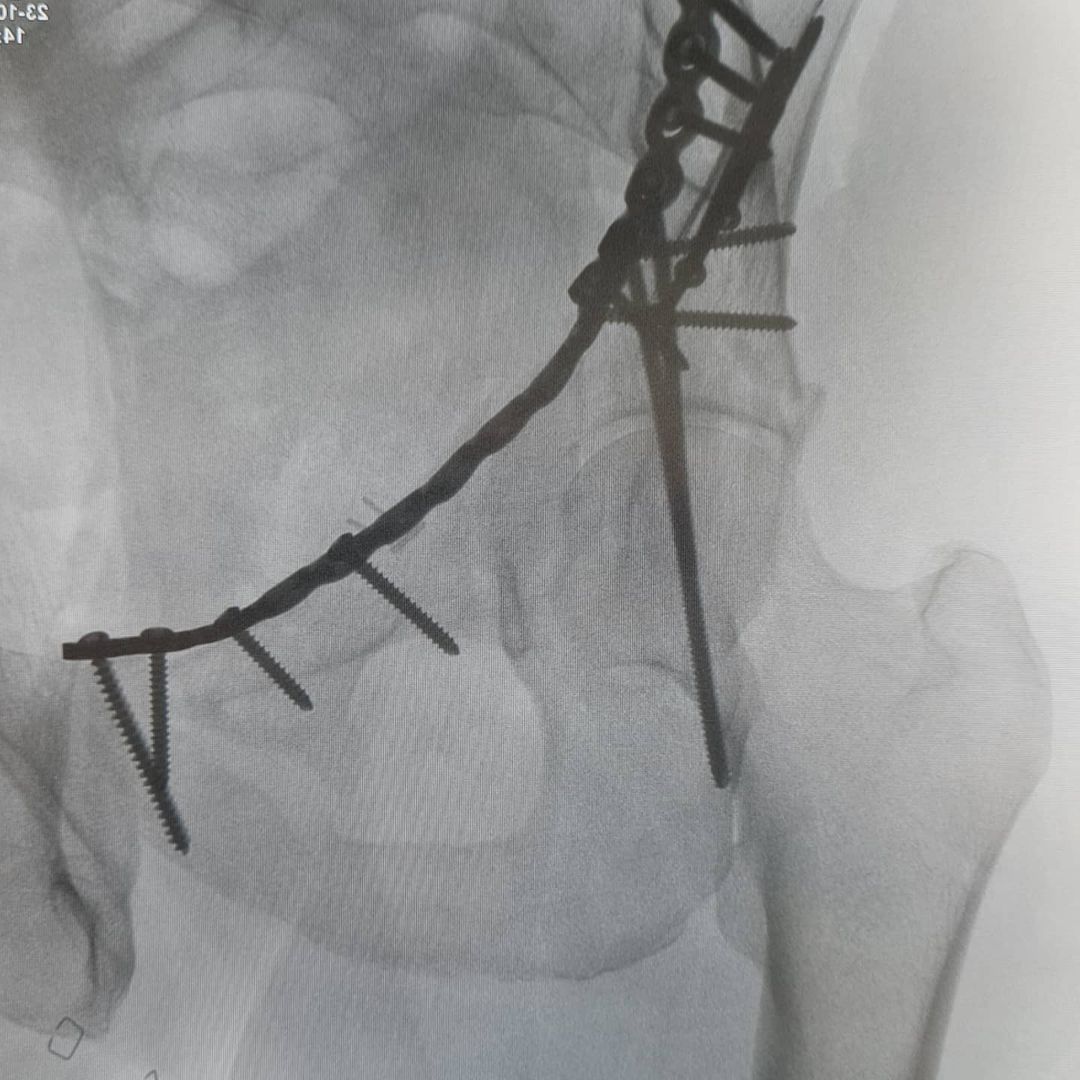

Y así se ha hecho la 'reparación' del interior de la pelvis que afectaba a sus 3 huesos ImageImageImage